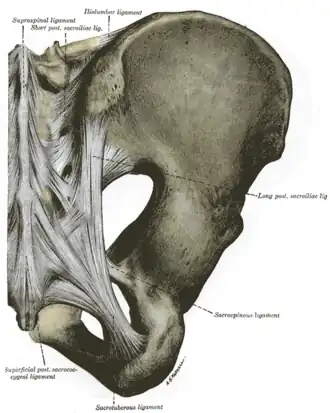

Articulations of pelvis. Posterior view.

Articulations of pelvis. Posterior view. -